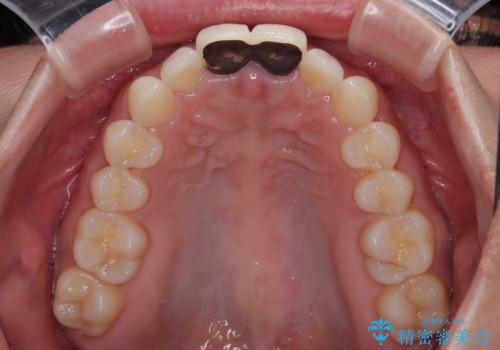

根管治療を行った後に、両歯ともに土台を植立し、オールセラミッククラウンにて補綴治療を行うこととしました。

黄ばみや厚みが改善され、まるで本物の歯のように調和した口元となりました。